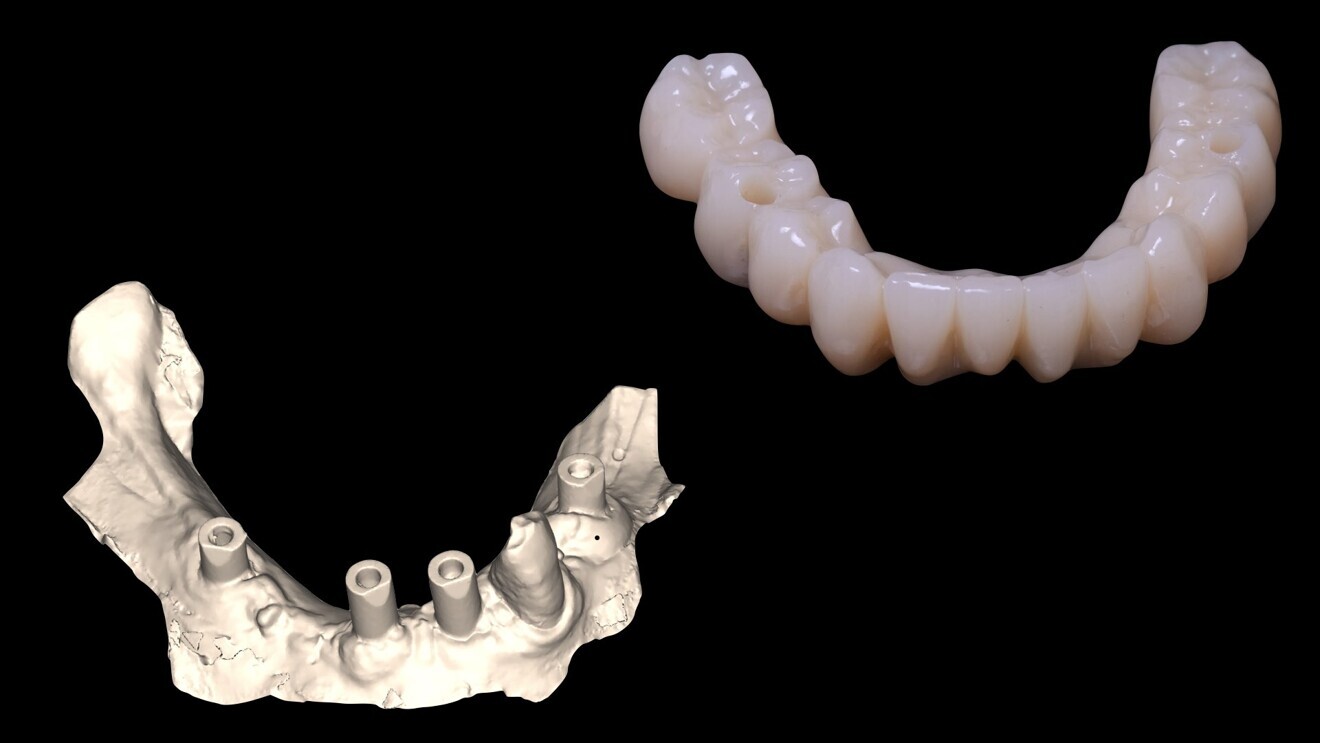

La réalisation d’un bridge transvissé usiné en PMMA avec vario-bases pour piliers multi-unit (Fig. 11) est usinée après l’utilisation de la caméra iTero pour l’empreinte des scan bodies au maxillaire.

Pour ce faire nous enregistrons la position des quatre scan bodies au maxillaire en postopératoire et le laboratoire superposera ce fichier STL, aux fichiers STL enregistrés initialement du maxillaire en occlusion avec la mandibule, ceci dans le but de mettre l’empreinte postopératoire avec scan bodies en occlusion avec le modèle mandibulaire, qui a déjà reçu un bridge provisoire transvissé quelques semaines auparavant.